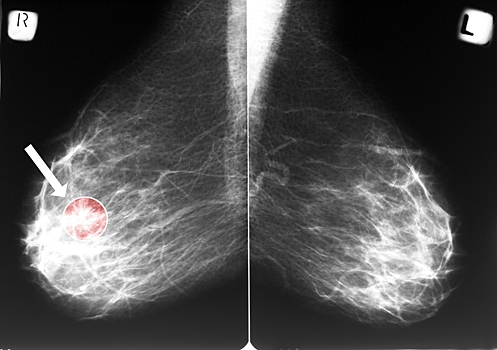

Американские ученые открыли новый метод лечения рака груди. Он поможет уничтожить 95-100% злокачественных клеток, сообщает Science Translational Medicine.

Исследователи создали препарат ErSO, который нацелен на белок-рецептор эстрогена. Именно данный белок присутствует в подавляющем большинстве опухолей молочной железы.

Уникальность данного метода заключается в том, что ErSO не касается клеток, в которых отсутствует рецептор эстрогена, и не влияет на здоровые клетки. Молекула влияет не только на сами раковые клетки, но и уничтожает метастазы.